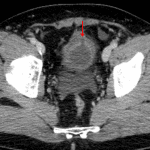

- Wall thickening of the anterosuperior bladder with a possible focal defect and adjacent small amount of low density free intraperitoneal fluid layering dependently in the pelvis

- Defect in the anterosuperior bladder with contrast spillage into the peritoneal cavity, layering dependently in the pelvis

- Intraperitoneal bladder rupture

Findings concerning for intraperitoneal bladder with a likely focal defect along the anterosuperior bladder wall. Recommend CT cystogram for further evaluation.

Intraperitoneal bladder rupture with a defect in the anterosuperior bladder wall.